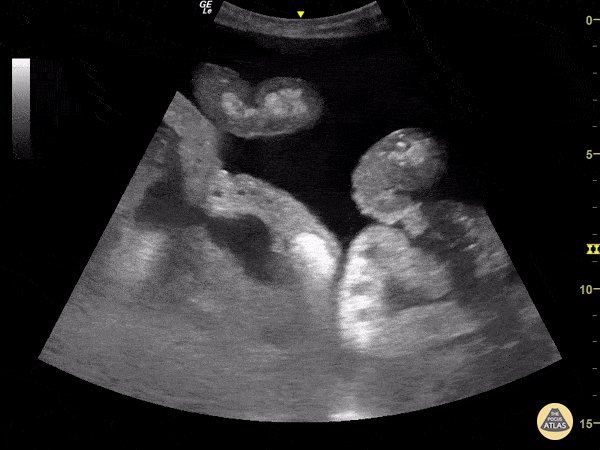

Making a thread of some POCUS gifs from @thepocusatlas

Will be referring to these during a basic POCUS workshop where learners practice scans on normal volunteers.

Non-scanning learners can pull up and show some abnormal examples in parallel with live demo of normal findings

13 - Normal kidney

14 - Moderate hydronephrosis

15 - Distended bladder

All images above from thepocusatlas.com , an amazing resource.